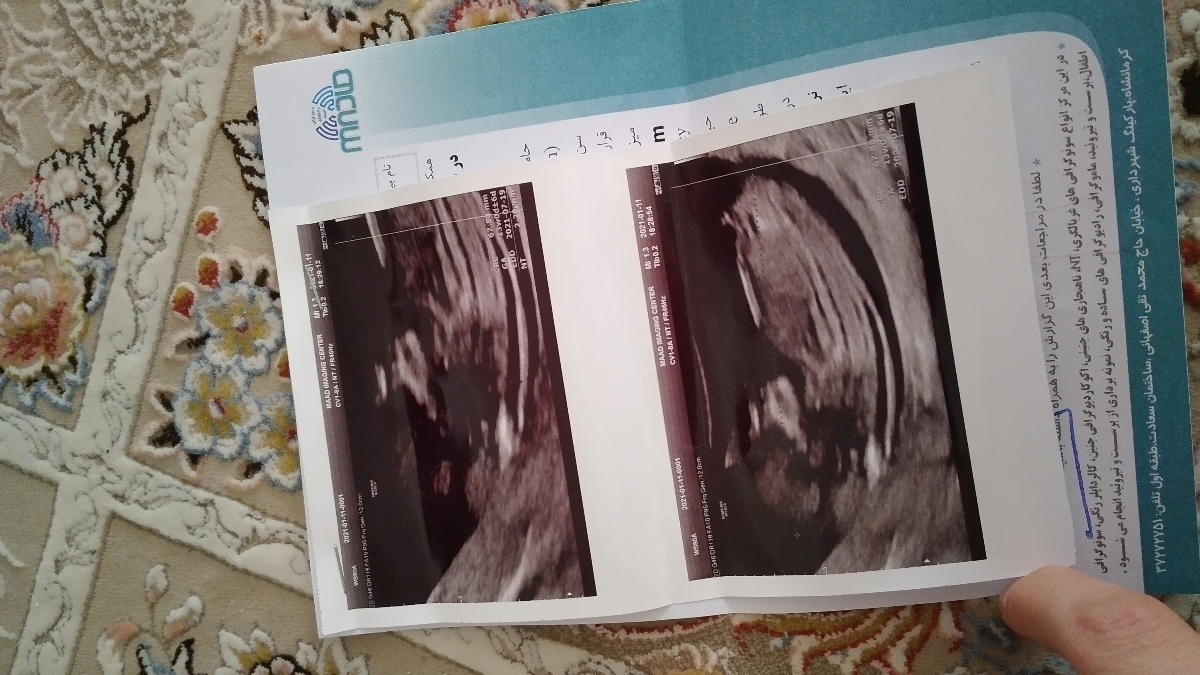

با سلام میخوام تفسیر آزمایش وسونوی غربالگری رو بدونم

سلام دوستان خیلی نگرانم امروز توی سونو و آزمایشات ان تی بالاس حالا به یه دکتر دیگه برای فردا منو ارجاع داده کسی تا حالا اینو مشکلی داشته بعدش چی بوده؟

سلام دوستان امروز سونو وآزمایشمو بردم پیش دکتر برام آمینو سنتز نوشت کسی انجام داده خطرناک نیست؟